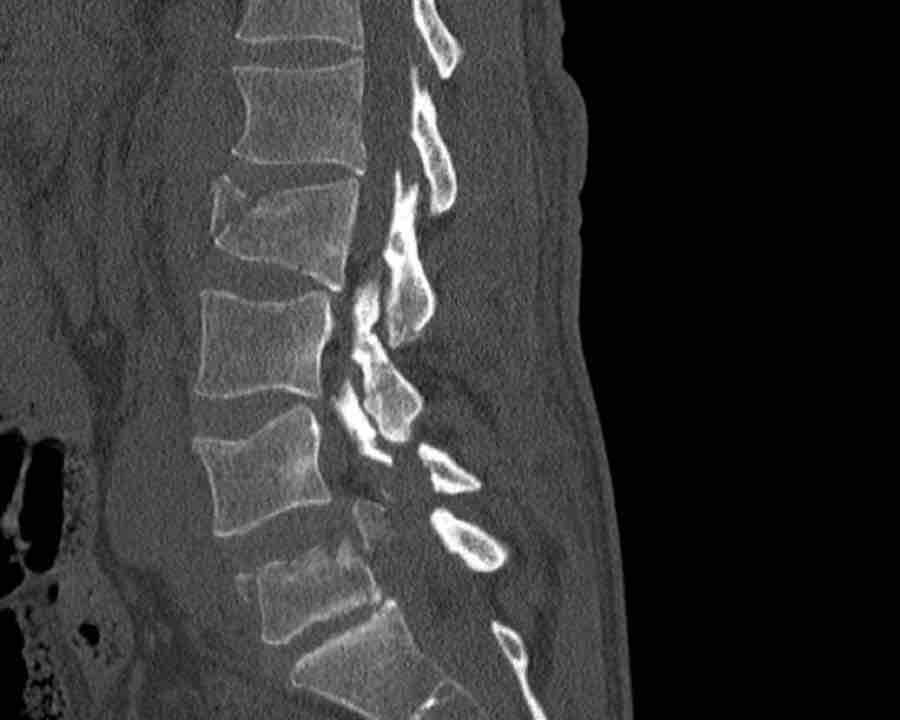

A2 Split fracture

A2 is a fracture of both endplates without involvement of the posterior wall of the vertebral body.

What is the highest AO-type of injury?

Findings:

- No C or B injury

- Fracture of the vertebral body with involvement of both endplates (1+1 points), no posterior wall involvement

Conclusion

injury type A2